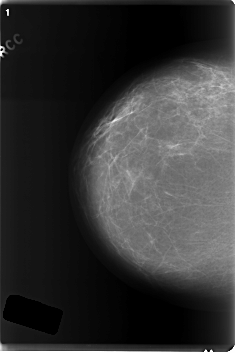

C_0219_1.RIGHT_CC

RIGHT_CC LINES 5992 PIXELS_PER_LINE 3992 BITS_PER_PIXEL 12 RESOLUTION 50 NON_OVERLAY